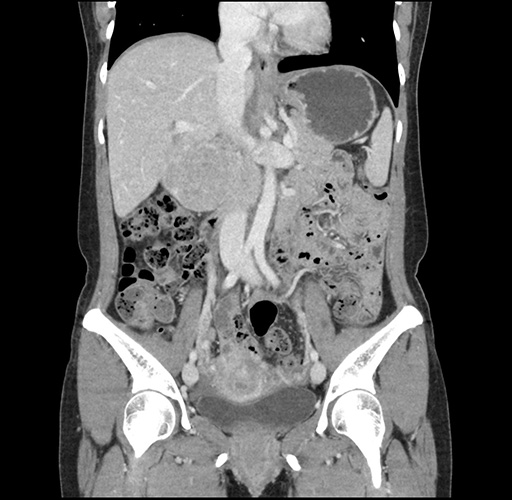

Imaging Analysis

Look through the patient's CT scan to identify any areas of concern for the necessary procedure.

Based on your CT findings, which issue(s) would give reason for "planned slowing down moment(s)" in this case?

Considering a standard left lateral sectionectomy procedure, what step(s) of the operation would you do differently in this case ?